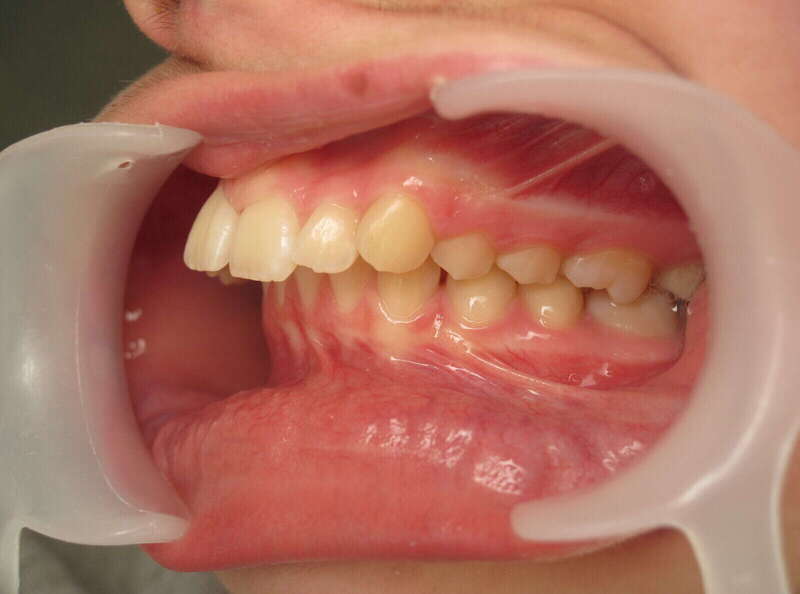

Ce cas d'adolescent illustre une stratégie de développement d'arcade réussie. Le patient présentait un encombrement massif et des inversions d'articulé rendant l'occlusion instable.

Le traitement a été réalisé avec des multibagues autoligaturantes, choisies pour leur capacité à générer des forces légères et continues, idéales pour l'expansion transversale. Cette approche a permis de corriger l'encombrement et les inversions d'articulé sans extractions dentaires, en remodelant simplement la forme des arcades.

Résultats clés :

• Transformation d'arcade : Passage d'une arcade étroite et encombrée à une arcade large et fonctionnelle.

• Occlusion optimale : Rétablissement d'un engrènement sain, protégeant les dents contre les usures anormales.

• Esthétique naturelle : Le sourire est élargi, harmonieux et parfaitement intégré au profil du patient.

C'est une démonstration de l'efficacité biologique de l'orthodontie moderne, qui privilégie la conservation dentaire et le respect des structures osseuses.